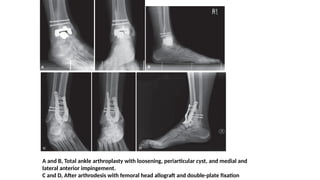

A and B, Total ankle arthroplasty with loosening, periarticular cyst, and medial and

lateral anterior impingement.

C and D, After arthrodesis with femoral head allograft and double-plate fixation

A and B,Total ankle arthroplasty with loosening, periarticular cyst, and medial and lateral anterior impingement. C and D, After arthrodesis with femoral head allograft and double-plate fixation